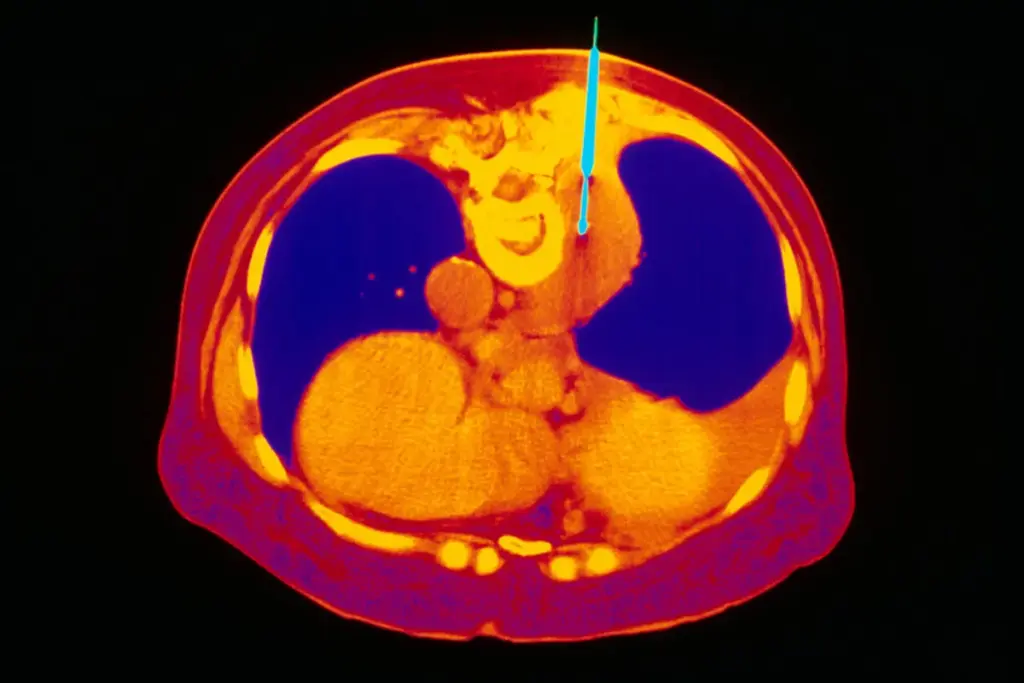

CT-guided biopsy is a common test for lung issues. But, it comes with some risks that patients need to know about.

A CT-guided biopsy is a precise medical procedure. It uses a CT scanner to guide a biopsy needle. This method targets specific areas, like the lungs, with great accuracy. We’ll explain the procedure, including the needles used and the steps involved.

What is a CT-guided Biopsy?

A CT-guided biopsy is a minimally invasive method. It uses a CT scanner to guide a lung biopsy needle into lung tissue. This ensures accurate tissue sampling for diagnosis. The CT guidance makes the procedure more precise, lowering the risk of complications.

3. Needle Insertion: The lung biopsy needle is inserted through the skin and guided to the target area using CT images.